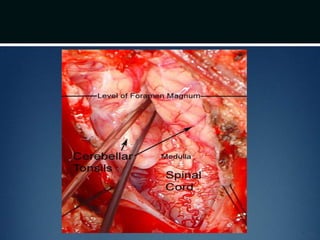

Posterior fossa decompression..

โ€ข Prone position and neck flexed

โ€ข Incision from below inion to the spinous process of

C2

โ€ข Avascular plane (nuchal ligament) b/t paraspinous

muscles followed down to bone and subperiosteal

dissection performed

โ€ข Moderate suboccipital craniectomy, width of the

foramen magnum followed by removal of posterior

arch of atlas

โ€ข Dura opened

โ€ข Arachnoid adhesions obstructing flow

removed and the floor of the 4th ventricle

examined

โ€ข Portion of occipital pericranium harvested

through a separate incision and duroplasty

performed